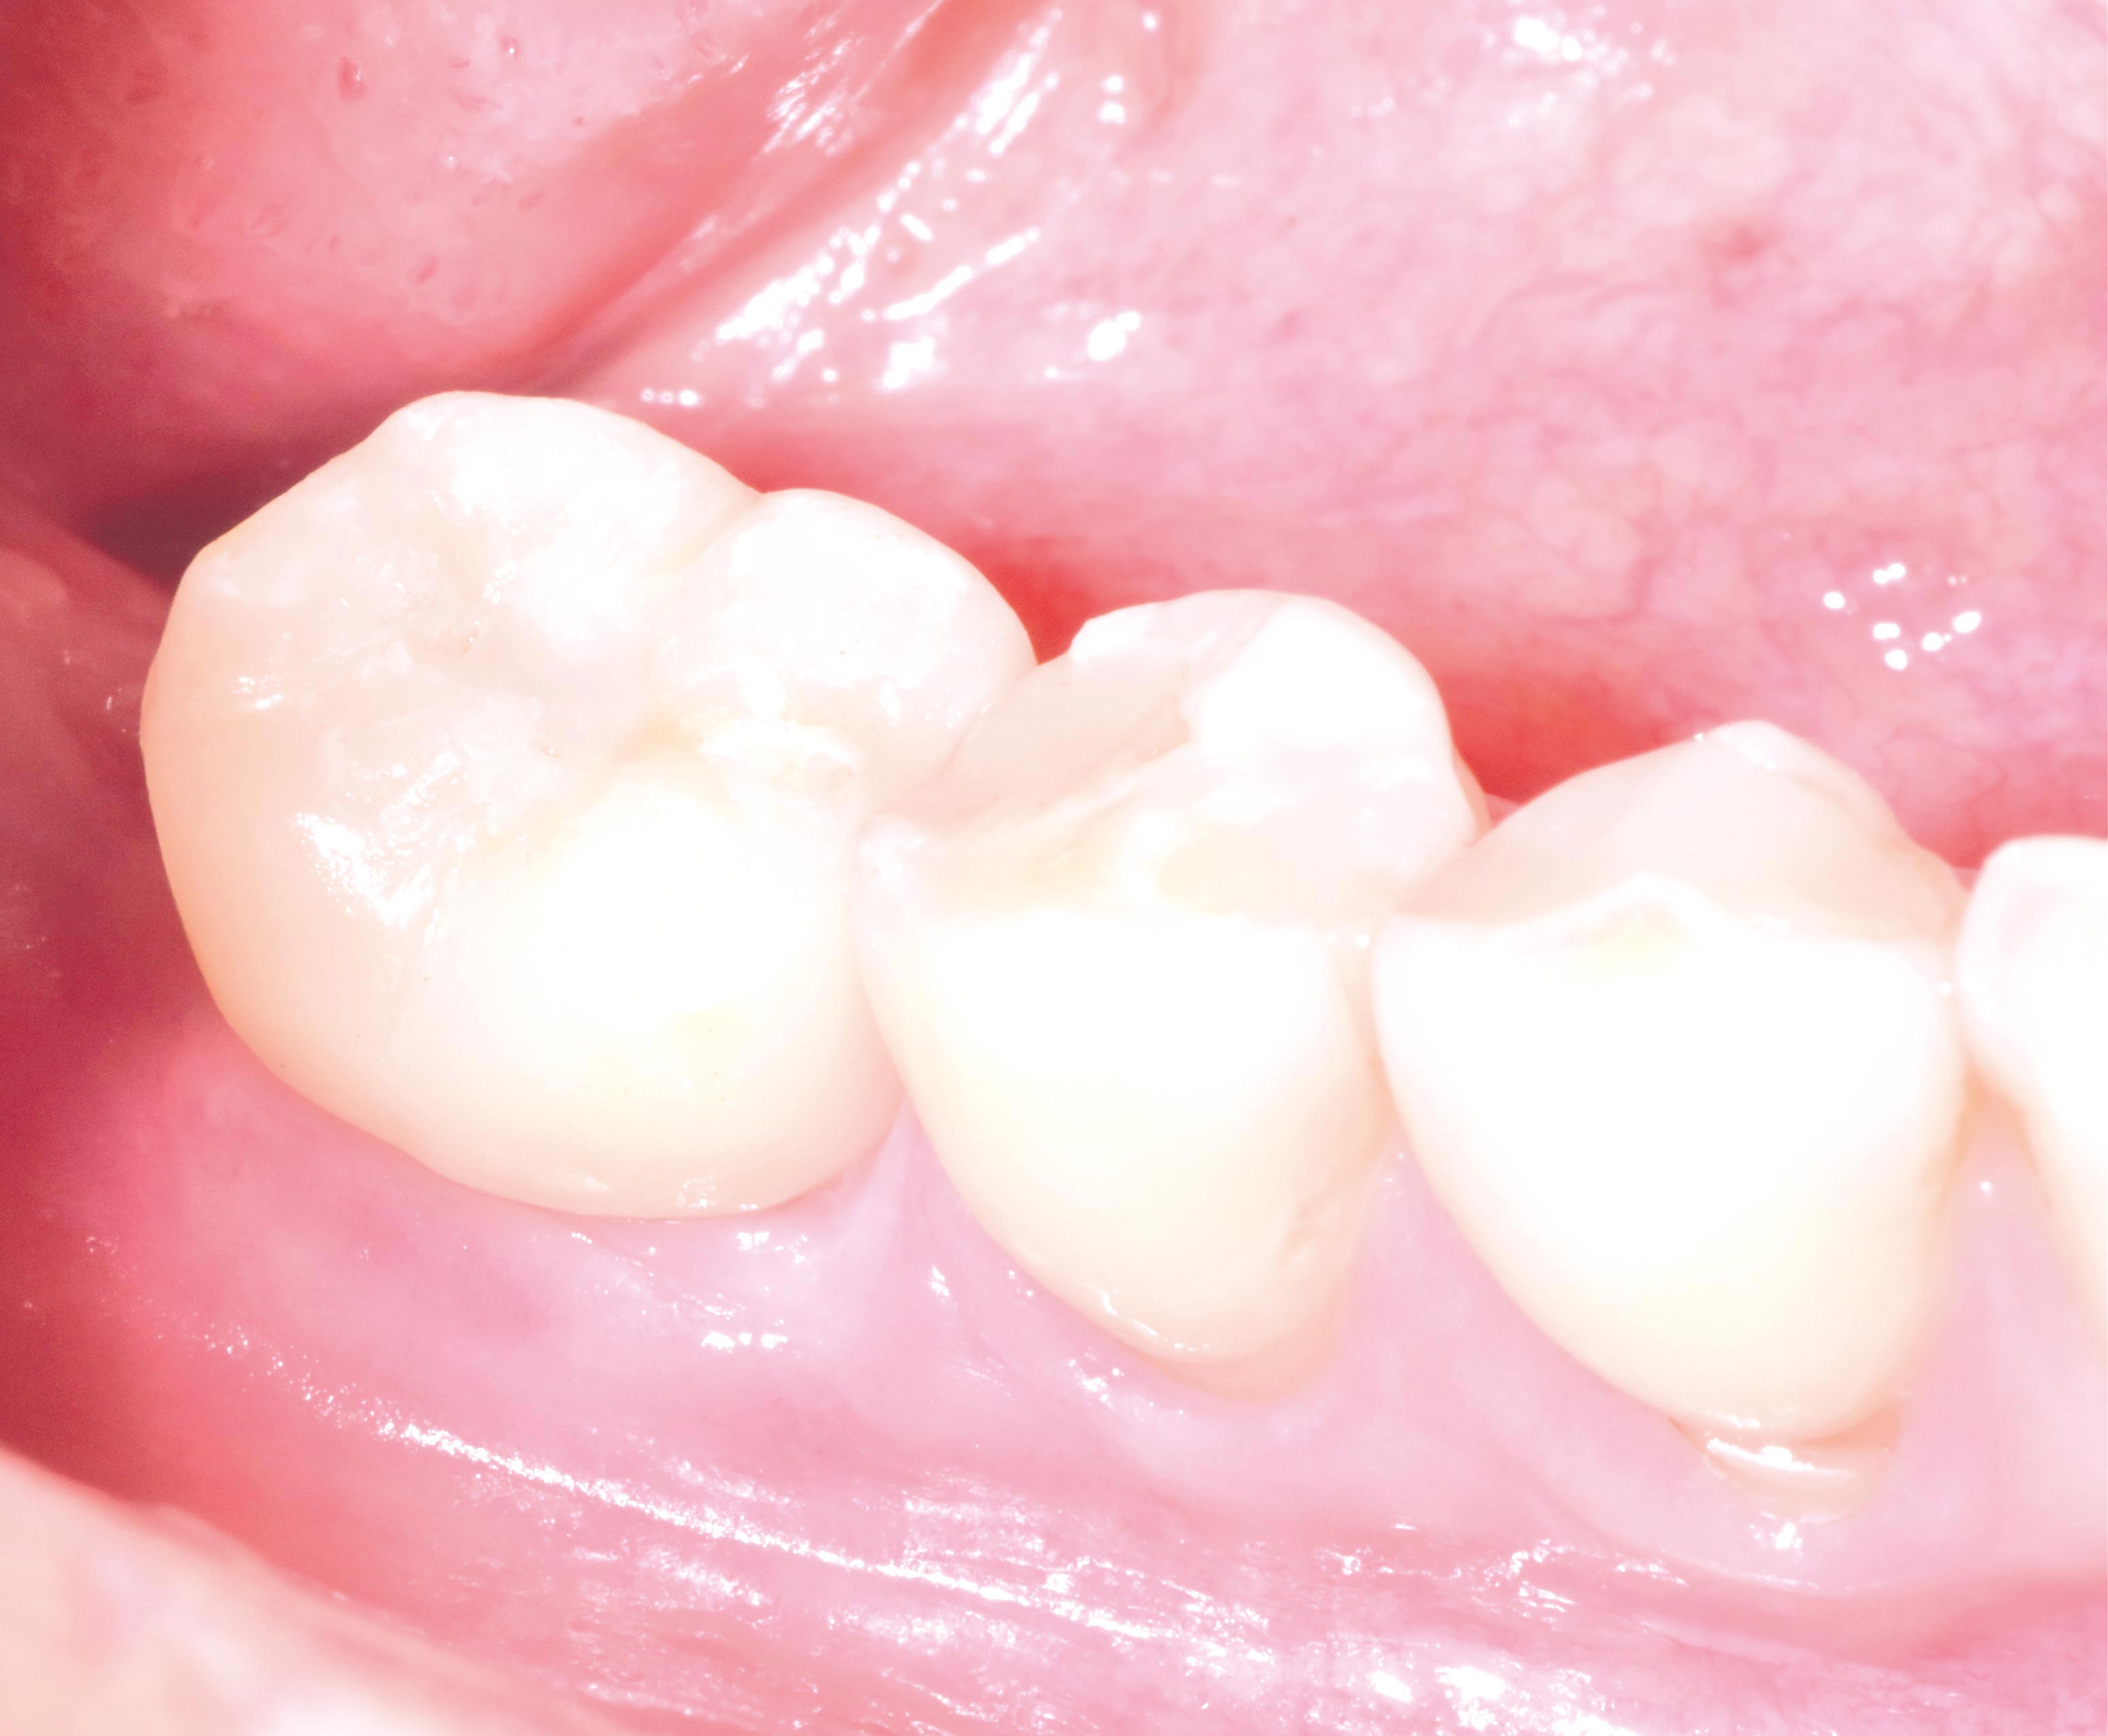

Initial clinical situation with single tooth gap in regio 21